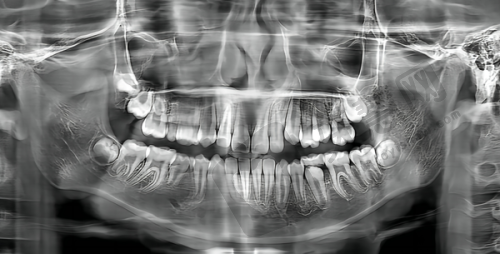

为给患者提供更精细、效率高治疗,常州美奥口腔医院引进一系列国内外新型口腔诊疗设备,这些设备代表当今口腔医学领域精良水平,为医院医疗服务提供有力保护。智能化口腔扫描仪是医院重要设备之一,它能快速、精细获取患者口腔三维数据,生成详细口腔模型。医生通过这些数据和模型能更直观了解患者口腔情况,制定更科学、合理治疗方案。与传统口腔取模方法相比,智能化口腔扫描仪微痛、快速、精细,大大提高患者就诊体验。激光治疗设备也是医院特色,在口腔治疗中可用于多种疾病治疗,如牙龈手术、牙齿美白、口腔黏膜病治疗等。它创伤小、出血少、疼痛轻、修复快,能有效减少患者痛苦,加速修复。例如在牙龈手术中,激光治疗设备可严谨切割牙龈组织,减少对周围组织损伤,术后患者肿胀和疼痛明显减轻,修复时间大大缩短。此外,医院还配备口腔摄影仪、智能化X光机等设备。口腔摄影仪可清晰记录患者口腔各个角度和细节,为医生诊断和治疗提供重要参考。智能化X光机能提供高清晰度口腔影像,帮助医生正确判断牙齿和颌骨病变情况,为治疗方案制定提供有力依据。